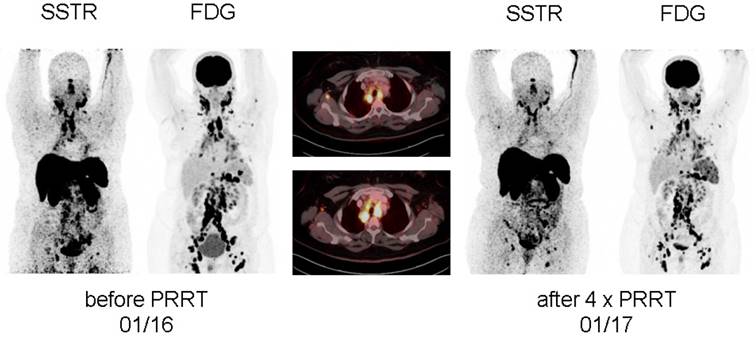

In patient #2, effects of PRRT resulted in a more short-lived pain relief. Whereas each treatment cycle reduced cervical pain, intensity started to recur 8 weeks after therapy. At the end of 4 PRRT cycles, although a decrease in serum activity parameters could be recorded (Table 2), no significant reduction in pain could be achieved. In parallel, imaging revealed stable disease regarding morphology (with non-significant reduction in size) as well as disease activity.

Figure 2

Display of [18F]-FDG-PET/CT and somatostatin receptor-directed PET/CT with [68Ga]-DOTATOC before and 1 year after initiation of peptide receptor radionuclide therapy with [177Lu] in patient #2. After a total of four cycles, stable disease (with a slight reduction in somatostatin receptor expression and increasing activity in the spleen) was recorded. Both PET projections are displayed with the same intensity.